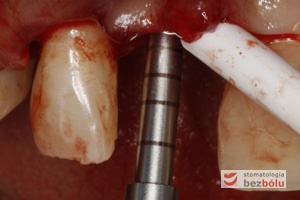

Sondowanie kości - kalibrowany marker pozwala na obliczenie gęstości pierwszego nawiertu

Sondowanie kości – kalibrowany marker pozwala na obliczenie gęstości pierwszego nawiertu